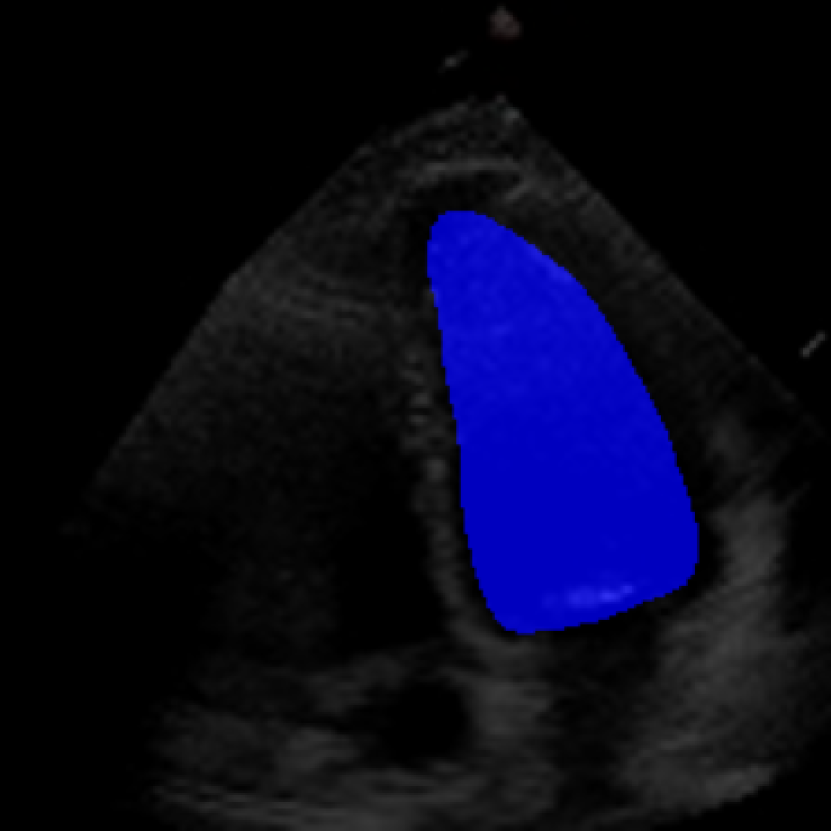

The 112x112 input is first resized to 299x299 as required by the Xception model. The Beat Extractor is then used to feed only whole beats to the LVEF estimation pipeline. A modified DeepLabV3+ model segments the left ventricle for every frame of the echocardiogram video (Figure LABEL:fig:segmentation). The area is measured, and a peak detector is then used to find the maximum (diastole) and minimum area (systole). The frame numbers corresponding to these extrema are recorded, and the video is clipped into smaller videos that go from diastole to systole. These smaller videos are independently fed to the Xception based feature extractor.

The ConFormer model demonstrated high performance in the estimation of Left Ventricular Ejection Fraction (LVEF) from echocardiogram videos (Figure 2). The model achieved a mean absolute error of 6.57 in LVEF prediction, indicating a high level of accuracy in its estimations (Table I). Notably, ConFormer outperforms the full video assessment of LVEF by EchoNet-Dynamic, a significant achievement given the model’s efficiency. With just 5.82 million parameters, ConFormer is significantly more efficient than existing models, making it a practical tool for real-world applications.